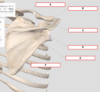

Identifiez

Scapula

Identifiez A

Fosse supra épineuse

Identifiez B

Processus coracoïde

Identifiez C

Acromion

Identifiez D

Cavité glénoïdale

Identifiez E

Épine scapulaire

Identifiez F

Fosse infra-épineuse